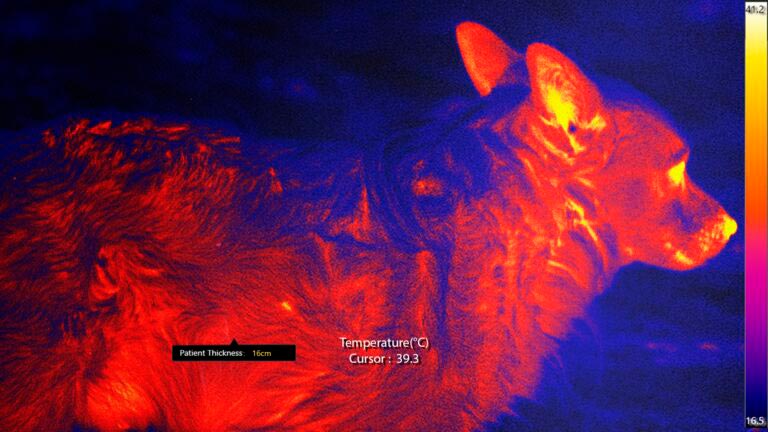

Imágenes Térmicas

Medir la variación de temperatura para ayudar a identificar áreas de posible enfermedad.

Detección Avanzada de Temperatura

El sistema de imágenes térmicas mide la variación de temperatura en el paciente, lo que indica posibles lesiones e infecciones.